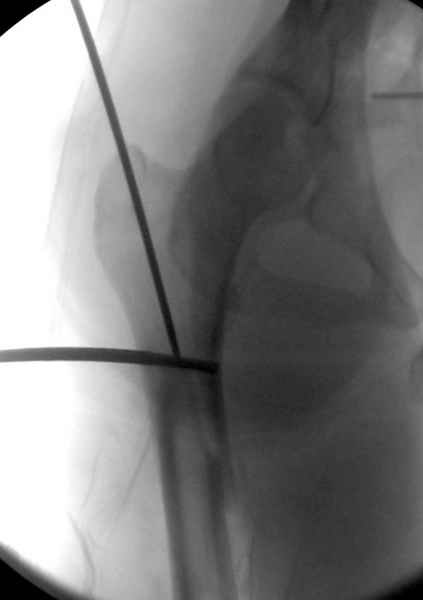

Второй случай тоже репозиция из малого доступа, больному 19 лет, множественные огнестрельные повреждениия конечностей, живота и черепа, правая конечность холодная, без пульсации. Ортопедический диагноз: огнестрельный перелом правого бедра. При срочной ангиографии повреждения сосудов не подтвердилось, конечность из-за ургентности состояния больного зафиксирована временным наружным фиксатором и больной оставлен на операционном столе для срочной лапаротомии хирургической службой.

Больной долго оставался нестабильным, только на 14 день удалось заменить на антеградный интромедуллярный штифт TFN (trochanteric femoral nail) SmithNephew. После неудачной попытки закрытой репозиции, несмотря на использование "joystick", проксимальный стержень от

наружного фиксатора, (перелом начал срастаться) репозицию провели из малого доступа, затем остальные этапы операции.

Случай был представлен из-за того, что больного оперировали после наружной фиксации и был риск инфекцирования через места проведения стержней (на снимках), прошло больше 3 месяцев, выписан из амбулаторной службы из-за отсутсвия надобности дальнейшего наблюдения.